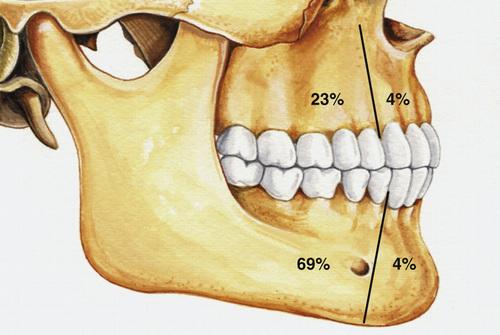

What are the three different clinicoradiographic presentations of ameloblastoma?

- conventional solid or multicystic (80%)

- unicystic (18%)

- peripheral or extraosseous (2%)